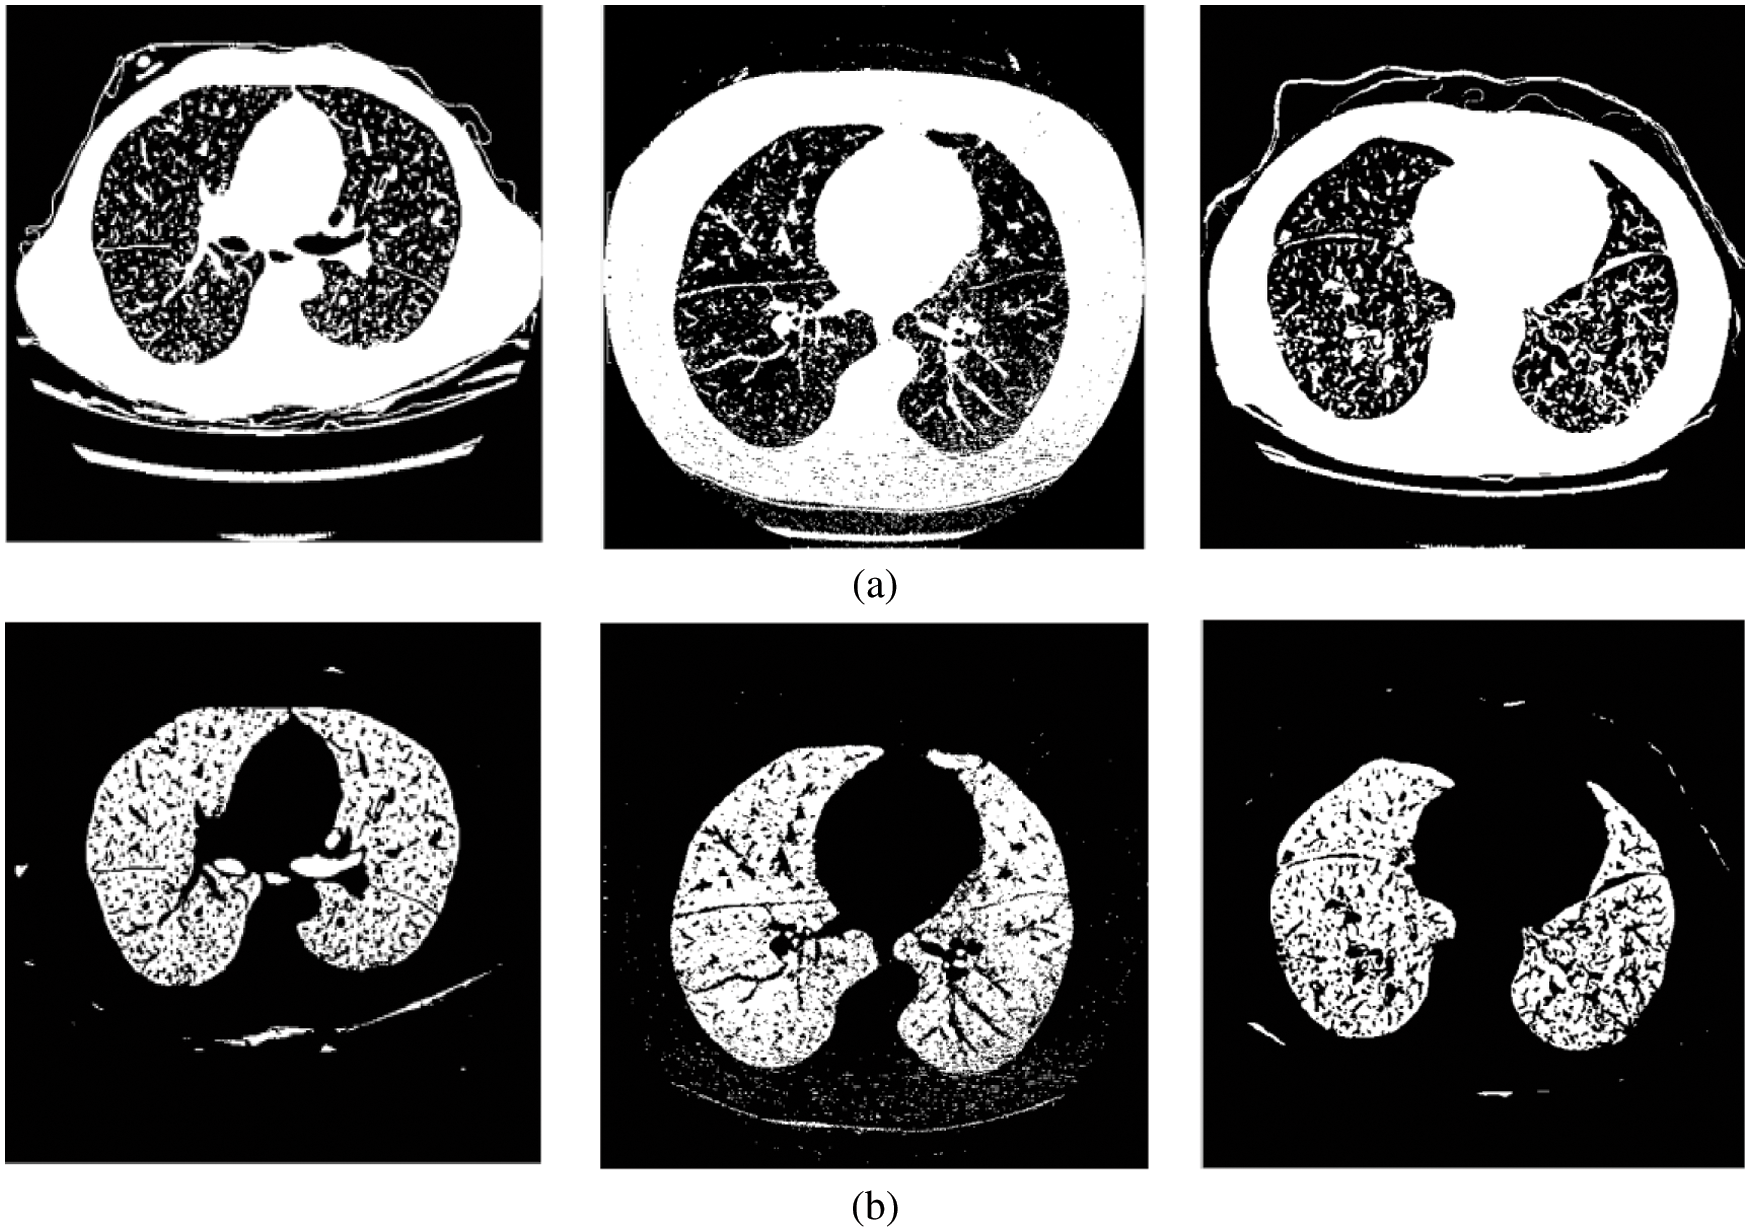

This module employs iterative thresholding and morphological operations to detect the left and right lung regions. The thresholding algorithm selects a gray value (threshold value) for binarization or thresholding of the image, as shown in Fig. 3a. The global thresholding approach cannot adapt to the local variations in the CT lung scans. Thus iterative thresholding [17,18] is applied.

Figure 3: (a) Threshold image (b) Lung region image